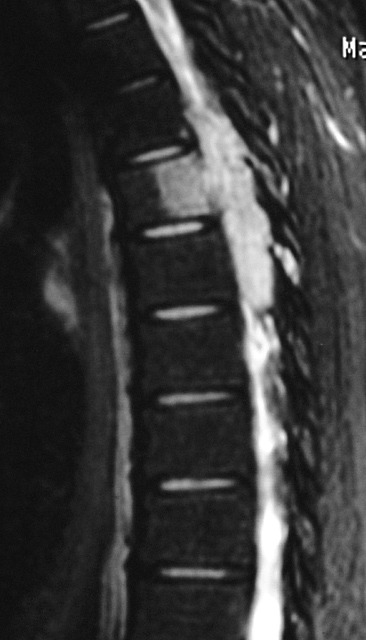

ГМ. СМ. Ганглионейробластома. +

Ганглионейробластома